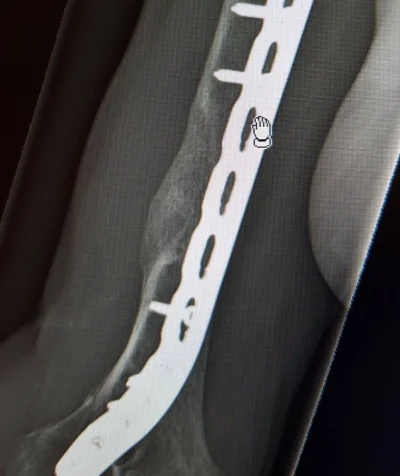

No karseeta ja karseeta, jos ei ny ihan jauhelihaksi menneestä puhuta, niin yleensä jos 10 sentin matkalla luuta on yli puolen kymmentä palaa niin alkaa tympimään.

Esim olkaluu ennen ja 3kk luusiirteen jälkeen.

Myös näitä viritelmiä ja mömmöjä on ja ne on ihan paskoja. Mutta väliaikaisina ratkaisuna esim tuossa olkaluussa.

Luusementtiä, joka on ehkä kumminkin enemmän sukua pikaliimalle...anteeksi, pleksiä..vai mitä lie, jotain polymetyyliakrylaattia.

Tietenkin jos luu on vain silppua, niin saa se yleensä sinne jäädä ja fiksataan vaan siitä ylitte, kyllä se siihen luutuu.

Mutta joo, riippuu luusta, missä kohti ja mitä luuta ja puuttuuko sitä vai onko silppua...ja onko avomurtuma tai eij.